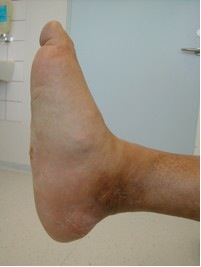

Se også foto af den akutte Charcots fod

Kilde: Foto og tekst til foto: Inge L. Kjær og Ugeskriftet for Læger; 170/33, s. 2442, "Den diabetiske Charcots fod" af Tomas Møller Christensen med flere., den 11. august 2008.